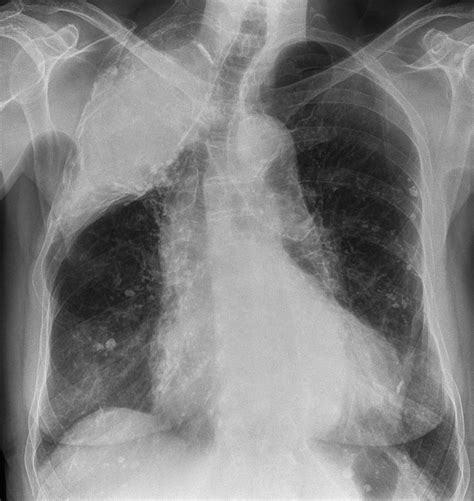

Diminished breath sounds can result from various conditions that affect the lungs and airways. Some of the most common causes include:

• Pneumonia: Inflammation and fluid accumulation in the lungs can reduce the transmission of breath sounds.

• Pleural effusion: The buildup of fluid in the pleural space can muffle breath sounds.

• Pneumothorax: Air in the pleural space can cause diminished breath sounds on the affected side.

• Atelectasis: Collapse of lung tissue can result in reduced breath sounds.

• Pulmonary fibrosis: Scarring and thickening of lung tissue can diminish breath sounds.